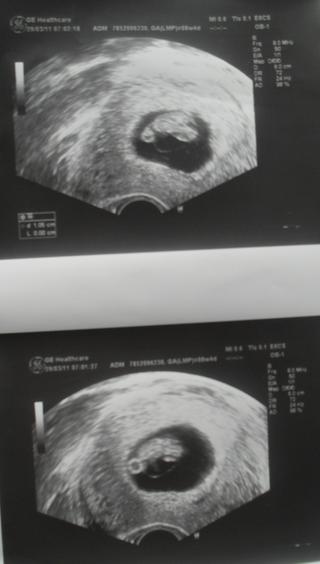

blackrose no malo asi 2cm to bolo fotene 29.3 tak už snáď podrástlo 🙂

@stellamiapiccola tak to je dost, lebo moje malo necely 1cm pred tyzdnom 🙂

@blackrose už som zvedavá čo bude noveho a videla som aj srdiečko ako bije 🙂

ahojte 🙂 vidim ze vela z vas tu vedie pochmurne rozhovory a mate to tazke, tak chcem trosku vylepsit naladu 🙂 ja som sa chcela len pochvalit a podelit o radost 🙂 zatial mi vyratali porod na 4.11. a vcera som bola prvy raz na sono a uvidela tu malu fazulku...s drahym sme obaja plakali ako male deti 😅 ...je to uzasny pocit...som prvorodicka a este donedavna som si nevedela predstavit ze budem mat dieta...ale teraz je to take silne, ze uz ho chcem mat tu na rukach a moct mu dat vsetko na svete...navyse mam obrovske stastie ze mi zatial tehotenstvo prebieha kludne, bez tych neprijemnych priznakov ako je nevolnost, zvracanie, nechutenstvo a pod...akurat vela mocim a prsia mam asi o 2 kila tazsie 😀 ale to sa este da zniest 😉 chcem